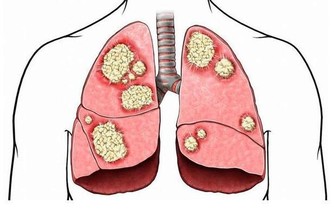

【降糖的時候減輕或者是不出現體重增加的藥物】

1、GLP-1受體激動劑,主要通過激活GLP-1受體發揮作用,因其降糖作用具有葡萄糖濃度依賴性,因此低血糖發生率極低,可在降低糖化血紅蛋白的同時降低體重。

2、二甲雙胍的藥物,主要是通過減少肝臟葡萄糖的輸出和改善外周胰島素抵抗而降低血糖,作為一種用於T2DM的有效藥物。

3、α-糖苷酶抑製劑,能夠通過減慢碳水化合物在小腸的吸收速度而降低餐後血糖,對體重的影響呈中性或輕度減輕。文章來源: /c/user/token/MS4wLjABAAAAARSimWY-YeSR6zdChv7Q3b5LxayKCC4NraQXzHRQGaE/?source=tuwen_detail